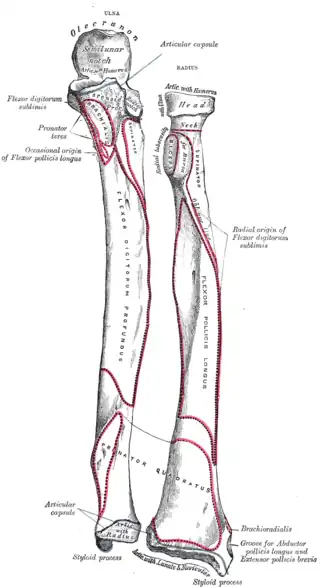

- Borders

The volar border (margo volaris; anterior border; palmar;) extends from the lower part of the tuberosity above to the anterior part of the base of the styloid process below, and separates the volar from the lateral surface. Its upper third is prominent, and from its oblique direction has received the name of the oblique line of the radius; it gives origin to the flexor digitorum superficialis muscle (also flexor digitorum sublimis) and flexor pollicis longus muscle; the surface above the line gives insertion to part of the supinator muscle. The middle third of the volar border is indistinct and rounded. The lower fourth is prominent, and gives insertion to the pronator quadratus muscle, and attachment to the dorsal carpal ligament; it ends in a small tubercle, into which the tendon of the brachioradialis muscle is inserted.

The dorsal border (margo dorsalis; posterior border) begins above at the back of the neck, and ends below at the posterior part of the base of the styloid process; it separates the posterior from the lateral surface. is indistinct above and below, but well-marked in the middle third of the bone.

The interosseous border (internal border; crista interossea; interosseous crest;) begins above, at the back part of the tuberosity, and its upper part is rounded and indistinct; it becomes sharp and prominent as it descends, and at its lower part divides into two ridges which are continued to the anterior and posterior margins of the ulnar notch. To the posterior of the two ridges the lower part of the interosseous membrane is attached, while the triangular surface between the ridges gives insertion to part of the pronator quadratus muscle. This crest separates the volar from the dorsal surface, and gives attachment to the interosseous membrane. The connection between the two bones is actually a joint referred to as a syndesmosis joint.

- Surfaces

The volar surface (facies volaris; anterior surface) is concave in its upper three-fourths, and gives origin to the flexor pollicis longus muscle; it is broad and flat in its lower fourth, and affords insertion to the Pronator quadratus. A prominent ridge limits the insertion of the Pronator quadratus below, and between this and the inferior border is a triangular rough surface for the attachment of the volar radiocarpal ligament. At the junction of the upper and middle thirds of the volar surface is the nutrient foramen, which is directed obliquely upward.

The dorsal surface (facies dorsalis; posterior surface) is convex, and smooth in the upper third of its extent, and covered by the Supinator. Its middle third is broad, slightly concave, and gives origin to the Abductor pollicis longus above, and the extensor pollicis brevis muscle below. Its lower third is broad, convex, and covered by the tendons of the muscles which subsequently run in the grooves on the lower end of the bone.

The lateral surface (facies lateralis; external surface) is convex throughout its entire extent and is known as the convexity of the radius, curving outwards to be convex at the side. Its upper third gives insertion to the supinator muscle. About its center is a rough ridge, for the insertion of the pronator teres muscle.[3] Its lower part is narrow, and covered by the tendons of the abductor pollicis longus muscle and extensor pollicis brevis muscle.

Muscle attachments

The biceps muscle inserts on the radial tuberosity of the upper extremity of the bone. The upper third of the body of the bone attaches to the supinator, the flexor digitorum superficialis, and the flexor pollicis longus muscles. The middle third of the body attaches to the extensor ossis metacarpi pollicis, extensor primi internodii pollicis, and the pronator teres muscles. The lower quarter of the body attaches to the pronator quadratus muscle and the tendon of the supinator longus.

Anterior surface of radius (at right)

Anterior surface of radius (at right) -